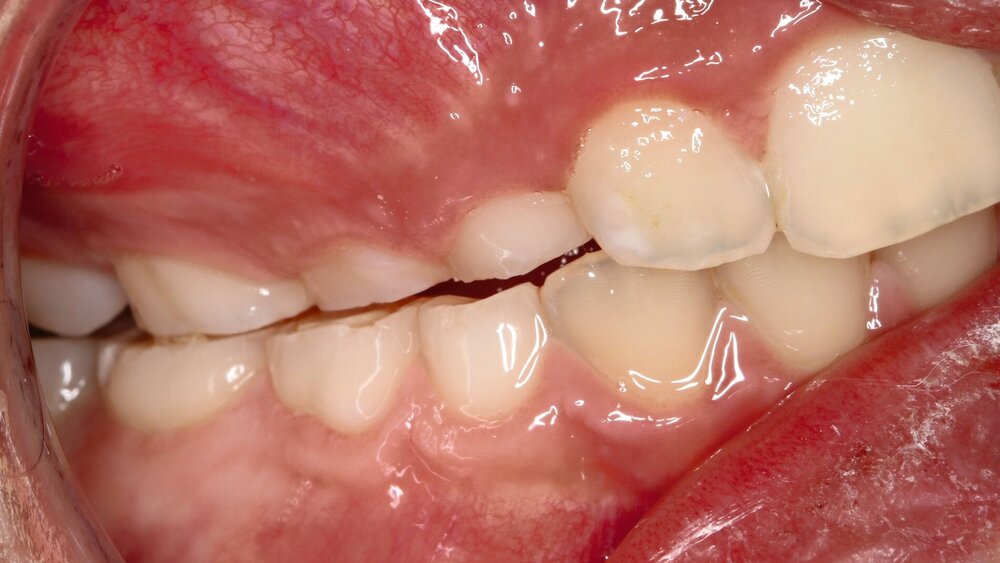

Glänzende Facetten, eine gleichmäßige Abnutzung der Schmelz-und Dentinflächen und das „Schlüssel-Schloss-Prinzip“ werden meist durch Attrition verursacht. Auch Abdrücke in den Weichgeweben wie Lippe und Wange beziehungsweise Frakturen an bestehenden Restaurationen der Antagonisten sind charakteristische Merkmale. Abrasionen hingegen werden extrinsisch durch Fremdkörper verursacht, wohingegen Erosionen auf die Einwirkung von Säuren zurückgehen. Säuren lösen Mineralien aus dem Zahnschmelz heraus. Dadurch kann Zahnhartsubstanz abgetragen werden. Typisch sind sogenannte okklusale Rillen, Abrundungen von Höckern und Auswaschungen (Abbildungen 1 und 2). Typisch ist hier auch der Zahnhartsubstanzverlust an Flächen, die normalerweise nicht okkludieren. Restaurationen zeigen sich erhaben und Amalgam erscheint glänzend [Wetselaar und Lobbezoo, 2016].

Eine präzise Zuordnung der Art des Zahnhartsubstanzverlusts ist häufig schwierig und nicht immer eindeutig möglich, da viele Patienten Mischformen aufweisen. Das „Schlüssel-Schloss-Prinzip“ ist aber das sicherste Diagnosekriterium für Bruxismus. Zur besseren Übersicht sind in Tabelle 1 die Merkmale von Erosionen, Attritionen und Abrasionen aufgelistet.